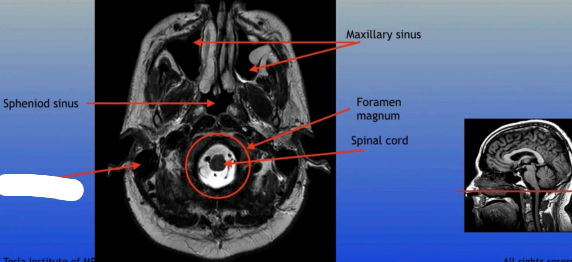

Maxillary Sinus

Sphenoid Sinus

Sphenoid Sinus

Mastoid Sinus

Maxillary Sinus

Foramen Magnum

Spinal Cord